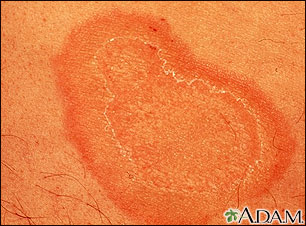

Eritema anular centrífugo-primer plano

Se llama eritema anular cuando el enrojecimiento aparece en el cuerpo en forma de anillos, como puede apreciarse aquí, en el antebrazo. Por lo general esta enfermedad no presenta síntomas, excepto por una picazón (prurito) leve y puede asociarse a enfermedades graves, pero en la mayoría de los casos nunca se descubre una causa subyacente.